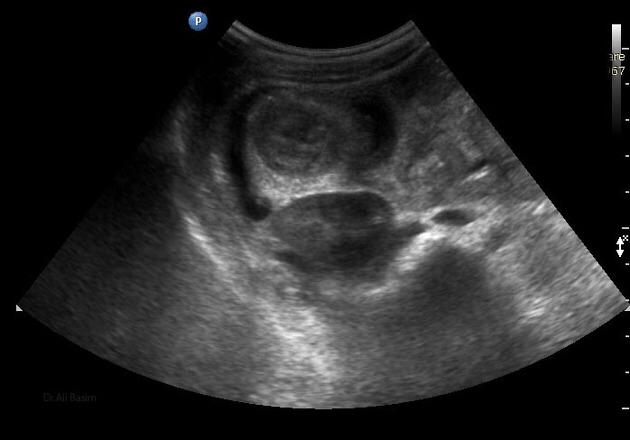

Ultrasonido de Glándula Tiroides

El término nódulo tiroideo se refiere a cualquier crecimiento anormal de las células tiroideas que forman un tumor dentro de la tiroides. Aunque la gran mayoría de los nódulos tiroideos son benignos (no cancerosos), una pequeña proporción de estos nódulos sí...